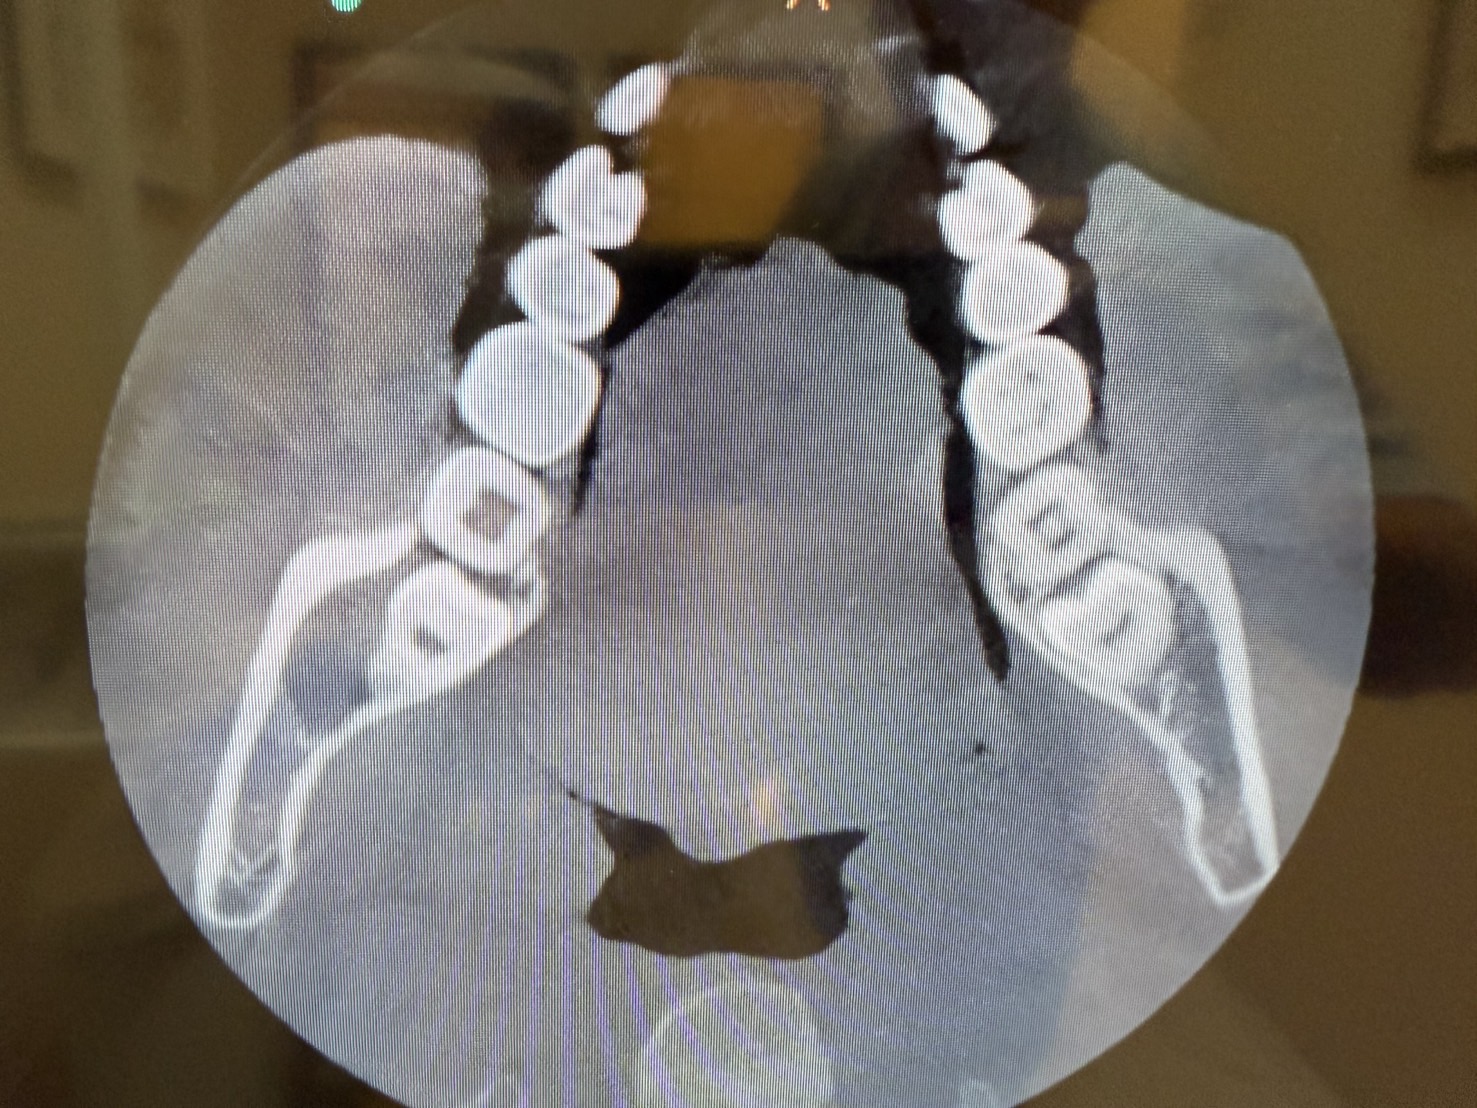

この患者さまは、親知らずに痛みがあり来院されました。こちらがCT撮影をした結果です。親知らずの横の下顎の骨の中に大きな膿の袋、嚢胞が形成されています。

X線、CTスキャン撮影の画像診断で嚢胞の正確な位置や大きさを特定し、嚢胞が周囲の骨や歯に与える影響を確認します。また歯の治療歴や外傷、や副鼻腔炎の治療歴なども詳細に確認します。そのうえで、治療計画をたてていきます。